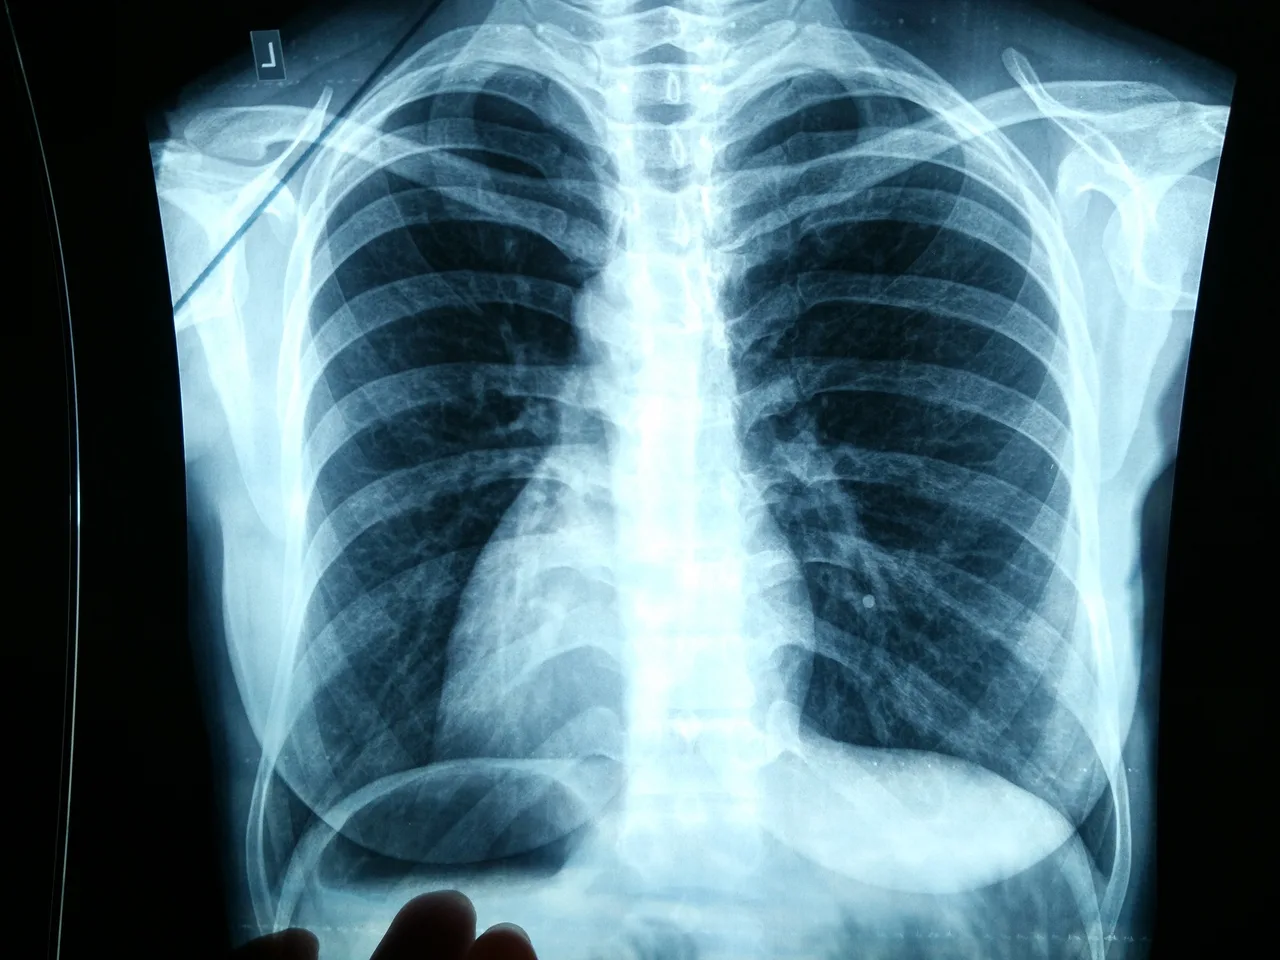

Врачи Свердловской области бьют тревогу: 85% случаев рака легких обнаруживают слишком поздно

С 3 по 9 ноября в Екатеринбурге и Свердловской области проходит масштабная Неделя профилактики рака легкого. Медицинское сообщество региона обращает внимание уральцев на тревожную статистику: этот вид онкологии лидирует по распространенности, а смертность от него достигает 85%, в первую очередь из-за поздней диагностики.